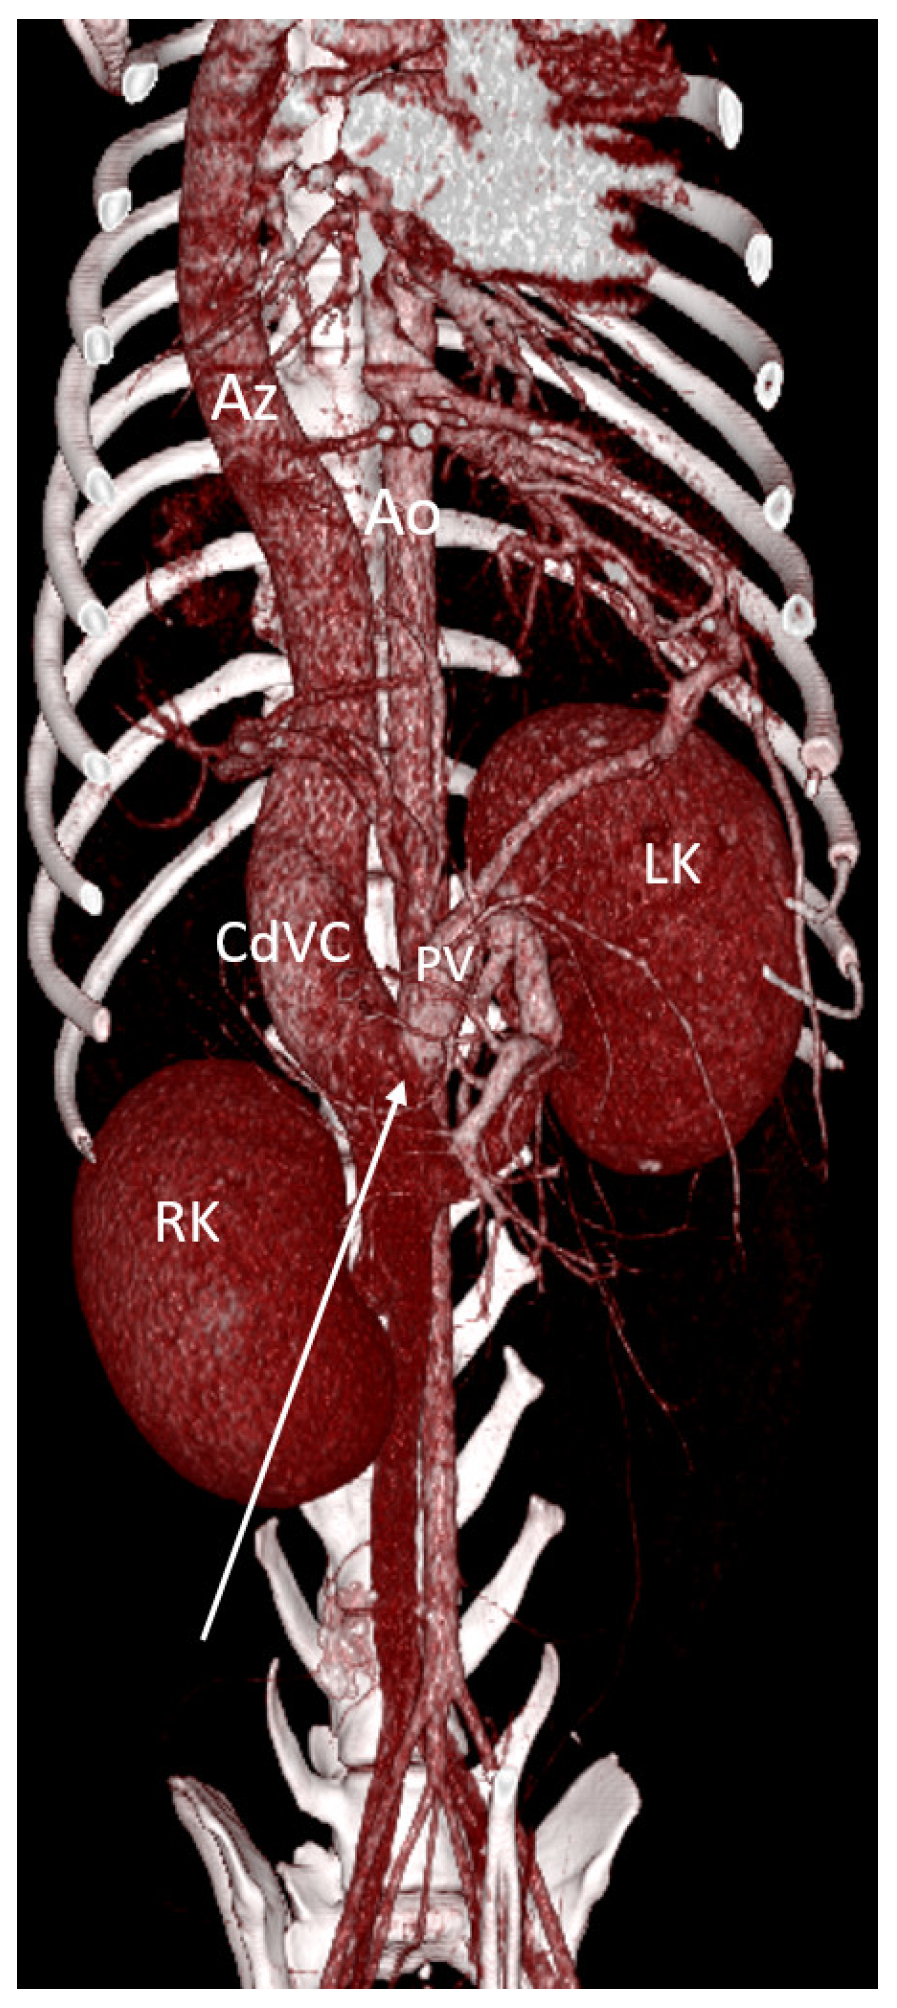

- Hunt, G.B.; Bellenger, C.R.; Borg, R.; Youmans, K.R.; Tisdall, P.L.; Malik, R. Congenital interruption of the portal vein and caudal vena cava in dogs: Six case reports and a review of the literature. Vet. Surg. 1998, 2, 203–215. [Google Scholar] [CrossRef]

- Zwingenberger, A.L.; Spriet, M.; Hunt, G.B. Imaging diagnosis-portal vein aplasia and interruption of the caudal vena cava in three dogs. Vet. Radiol. Ultrasound 2011, 52, 444–447. [Google Scholar] [CrossRef] [PubMed]